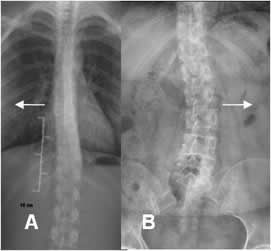

Fig 10. Asimetría espinal.

A y B: Rx AP. Desviación en los ejes de la columna. En A dorsal derecha y en B lumbar izquierda, pero de poca magnitud por asimetría.